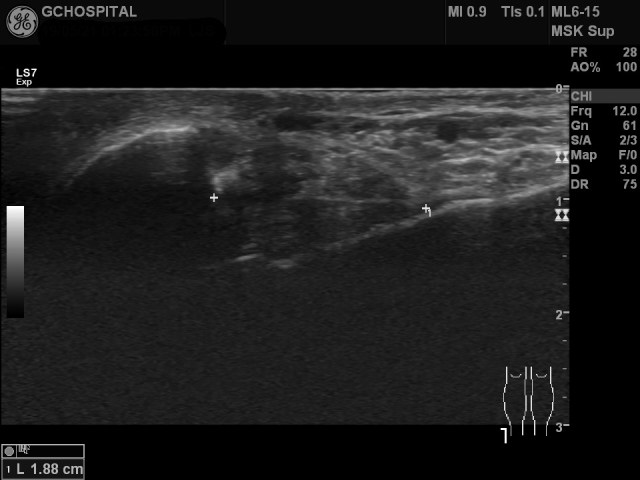

여기에 더해 경험이 부족해서 정확한 자세를 취하지 않아서 잘 안보이는 경우도 있는데, anterior talofibular ligament는 plantarflexion 한 상태에서, calcaneofibular ligament는 dorsiflexion을 취한 상태에서 검사하는게 영상의 질을 향상시키는데 도움이 됩니다.

실제로 anterior talofibular ligament가 발목을 어떻게 구부리는가에 따라 길이가 변하는지 초음파영상에서도 확인할 수 있습니다. 인대를 더 길게 늘인 상태에서 관찰해야 인대 자체의 확인도 쉽고, 인대의 손상여부도 민감하게 확인할 수 있습니다.

Anterior talofibular ligament는 위와 같이 platarflexion한 상태에서 훨씬 더 잘 관찰할 수 있는 반면, calcaneofibular ligament는 반대로 dorsiflexion 시 더 길어지고, 잘 보입니다.